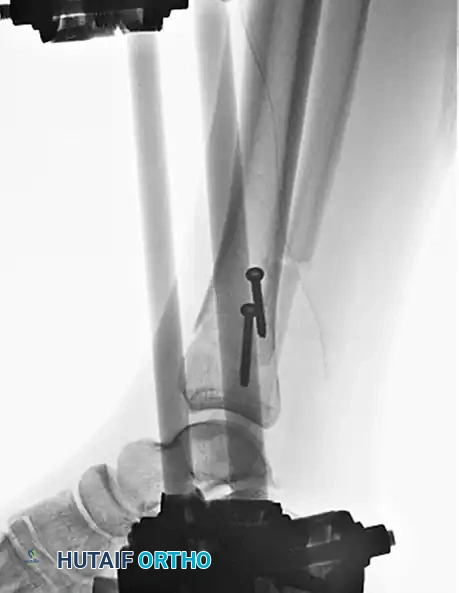

In the context of severe open fractures, interfragmentary screw fixation is an invaluable temporizing or supplementary measure. When applying a uniplanar external fixator to an open fracture, coronal plane stability can sometimes be difficult to control.

In such scenarios, large butterfly fragments or displaced metaphyseal spikes can continue to endanger the overlying soft tissue envelope. Anatomical reduction of the tibia and the strategic placement of interfragmentary lag screws can provide immediate stability as an adjunct to the external fixator.

Pitfall: Avoid complete interfragmentary fixation of open diaphyseal fractures neutralized only by external fixation, as this construct often yields poor long-term results due to stress shielding and inadequate mechanical support. Mixing these two systems is generally reserved for intraarticular fractures with shaft extensions, where screws are strictly confined to the periarticular region.

* Blocking (Poller) Screws: The strategic placement of blocking screws in the wide metaphysis artificially narrows the medullary canal, guiding the nail trajectory and preventing translation of the fragments.